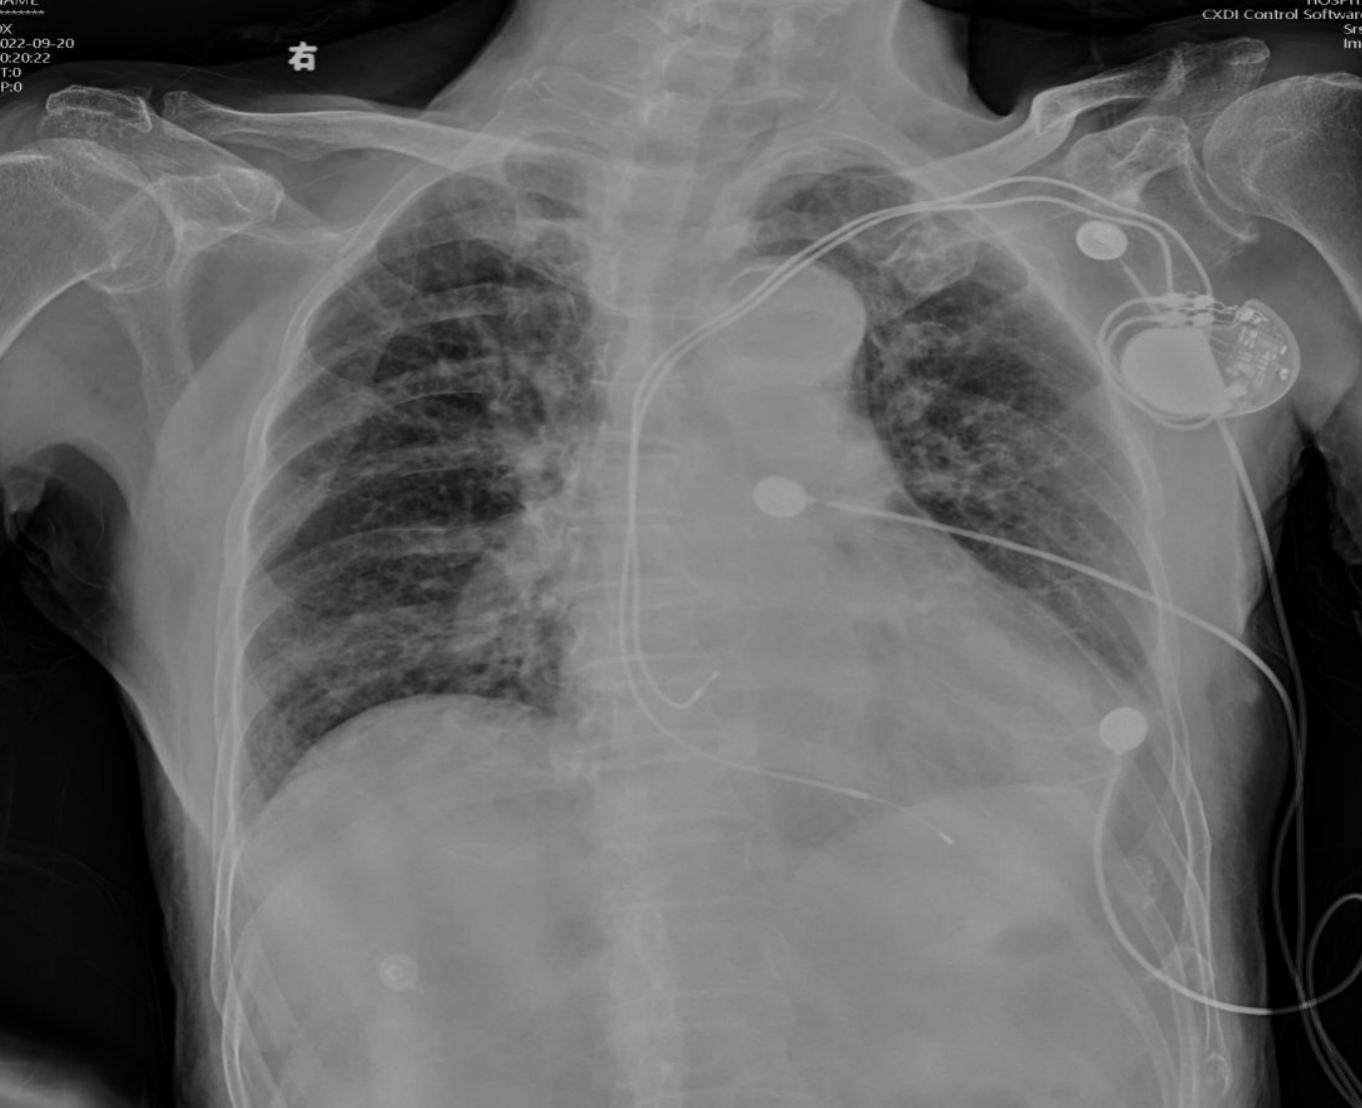

心电图显示,林爷爷有频发房性早搏,短阵房性心动过速,心肌缺血。同时,他体内的心脏起搏器已使用了5年,平时未能定期复诊,状况难料。

胸部影像片:心衰,肺间质水肿,见胸壁起搏器

“高龄患者在全身麻醉下,各项身体机能会发生变化,并且起搏器工作状态无法评估。通俗一点说就是,起搏器平时为备用状态,万一心律失常,需要启动起搏器,但如果起搏器电量不足,就会相当危险。” 傅向军说。

于是,傅向军紧急请心脏重症科会诊。会诊意见认为,起搏器工作状态未知,需要1-2天时间检测电池电量,而患者可能等不及了。经过与患者家属详细沟通,团队决定迎难而上,为林大爷进行气管插管全麻下异物取出手术。